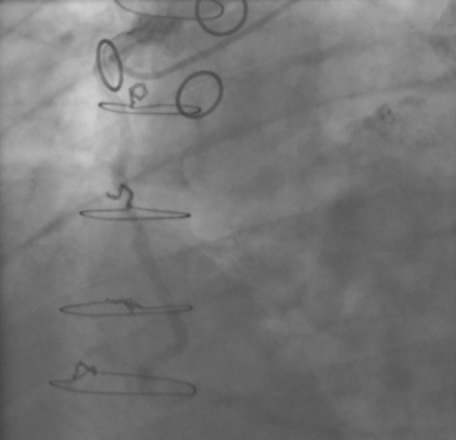

In the past, surgeons used rings to mark the ostia of the vein grafts substantially aiding the angiographer to localize the vein graft ostia during angiography. However, nowadays, it is not a usual practice. The lack of marker can increase the contrast use and radiation particularly in patients without the knowledge of the types and number of vein grafts. As mentioned earlier, right coronary grafts have usually a right sided take off from the aorta. Therefore, using standard view, left anterior oblique (LAO), which is used for right coronary artery catheterization is the view of choice. Left coronary bypass grafts have usually anterior take off. Therefore, a right anterior oblique (RAO) makes it easier to engage the left-sided vein graft ostia preventing foreshortening of the catheter tip. Using RAO, the catheter tip should be oriented to the right side of the screen. The vein grafts to the left system is based on the anatomical proximity of the native coronary to the aorta. Therefore, LAD graft ostia are usually closest grafts to the aortic valve followed by diagonal and circumflex grafts. Circumflex graft ostia usually have the highest take off from the aorta. There are occasional cases with different take off making vein graft angiography difficult. In such a situation, the angiography catheter has to be probed across the aorta in different level in order to engage the ostial vein graft. A non-selective strong contrast injection or aortogram may be necessary to delineate the unusual take off of missing vein grafts or documenting total occlusion of missing vein grafts. Total occluded vein grafts usually have a residual knob in the aorta that can be seen during angiography.

The most commonly used catheters for left heart catheterization and vein graft angiography can be seen in Figure 1 and Figure 4-13. Most of the vein grafts have horizontal take off and can be successfully engaged using a commonly used Judkins right number 4 (JR4) catheter. The JR4 catheter is the most commonly used catheter for the engagement of the right coronary ostium with horizontal take off. However, many vein grafts have unusual take off requiring different catheters. Many right coronary vein grafts have steep inferior take off making the ostial engagement with JR4 difficult or impossible (Figure 10). In such a scenario, a multipurpose catheter which has a shallow angulation is the best choice (Figure 11). The second major challenge in engaging vein graft ostia, particularly vein grafts supplying the left coronary arteries, is the shape of the aorta. A large aorta can make it very difficult for the JR4 catheter to reach the ostial vein grafts. In such a situation, Amplatz (AR) right and left (AL) catheters can be very helpful to reach the vein graft ostia. Amplatz catheters have a larger primary curve and have been used successfully in unusual superior take off of left coronary arteries or vein grafts and in large aorta. Amplatz catheters are available in different sizes (from smaller to larger curve: AR 1, AR2, AL2, AL2 and AL3). Occasionally, a very superior take off of a vein graft requires specially designed bypass graft catheters. Amplatz catheters are also extremely helpful in engaging native right coronary ostium with anterior take off.